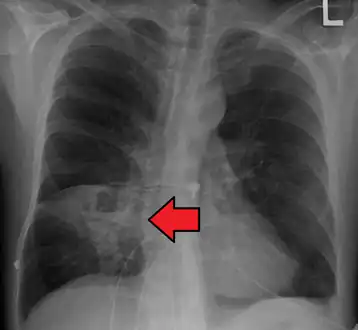

Lung abscesses are often on one side and single involving posterior segments of the upper lobes and the apical segments of the lower lobes as these areas are gravity dependent when lying down. Presence of air-fluid levels implies rupture into the bronchial tree or rarely growth of gas forming organism.

Pulmonary abscess on CXR -